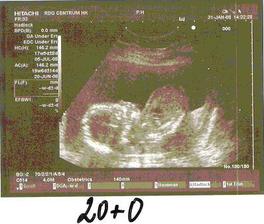

31.1. jsme byli na velkém ultrazvuku a vypadá to, že máme v bříšku pěkného čertíka Kubíka 🙂

9.9. tripple testy, výsledky nejsou OK, máme přijít na podrobný UZ a tři týdny na další, paní doktorce se tam stále něco nezdá, proto nás 21.10. poslala na amnio a kordocentézu, za týden máme výsledky, prý jsou v naprostém pořádku, tak už se můžeme těšit na našeho druhého chlapečka